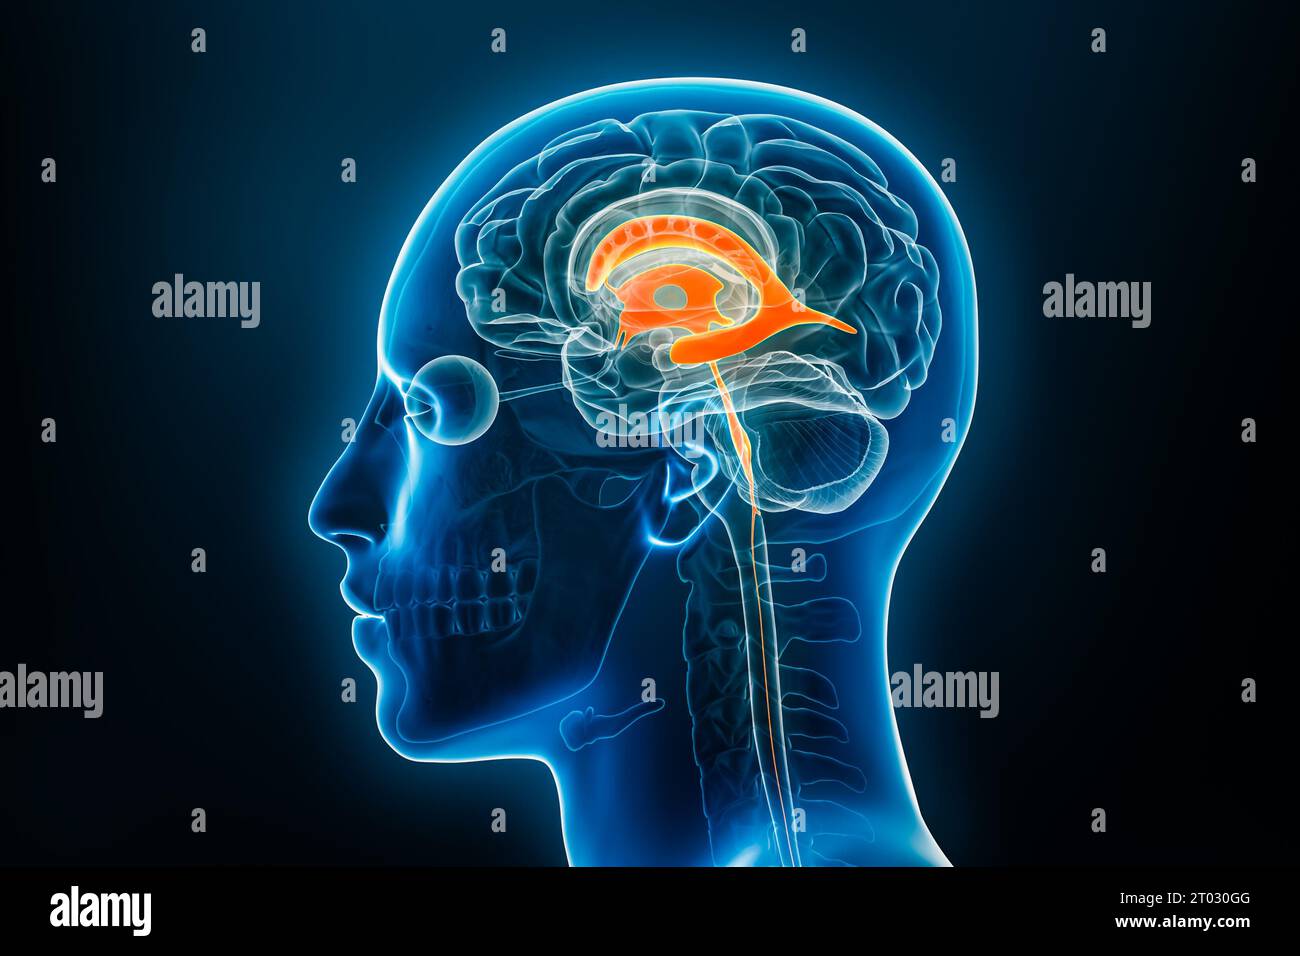

RF2T030GG–Röntgenlaterale Darstellung der Hirnventrikel 3D-Darstellung mit Körperkonturen. Anatomie des menschlichen und ventrikulären Systems, Medizin, Biologie, Scienc

RF2T7NGWH–Ventrikel und zerebrales Aquädukt laterale Röntgenansicht 3D-Rendering-Illustration. Menschliches Gehirn und Ventrikelsystem Anatomie, Medizin, Gesundheitswesen, Scienc

RF2T7NGWK–Ventrikel und zerebraler Aquädukt lateral in Farben Röntgenbild-3D-Rendering-Illustration. Menschliches Gehirn und Ventrikelsystem Anatomie, medizinisch, gesund

RF2T7NGWW–Ventrikel und zerebraler Aquädukt in Farben Röntgenprofil Nahansicht 3D-Rendering-Illustration. Anatomie des menschlichen Gehirns und des Ventrikelsystems, medizinisch,